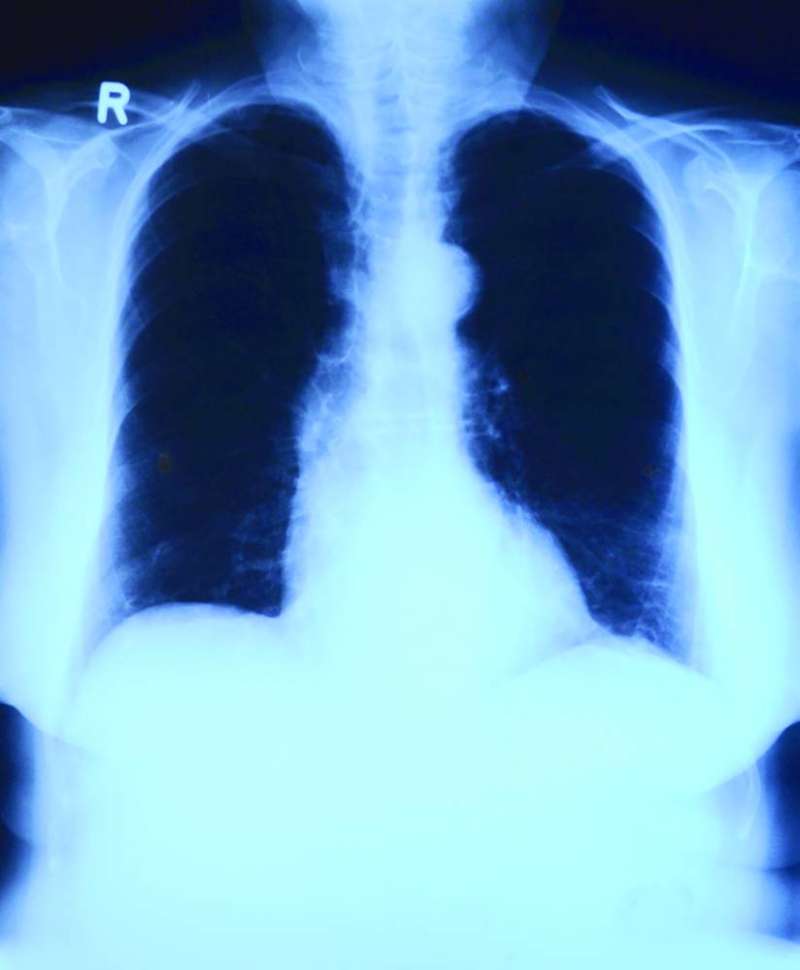

أعلن الطبيب الروسي ألكسندر مياسنيكوف، أن سرطان الرئة يبقى أكثر أنواع السرطان انتشاراً في العالم، سواء من حيث الإصابات أو الوفيات.

وأشار مياسنيكوف في برنامج تلفزيوني، إلى أن سرطان الرئة في المراحل المبكرة لا تظهر له أي أعراض، وفي مراحله المتقدمة أعراضه شبيهة بأعراض عدد من الأمراض.

وأضاف أن أكثر أعراض سرطان الرئة انتشاراً هي السعال، بحة في الصوت، سعال مزمن، ألم في الصدر، ضيق في التنفس، تكرر الإصابة بأمراض في الجهاز التنفسي - التهاب الشعب الهوائية، والالتهاب الرئوي، والتعب، وفقدان الشهية، والفقدان غير المبرر للوزن.

ووفقاً له، يمكن تشخيص سرطان الرئة في مراحله المبكرة باستخدام التصوير المقطعي الحاسوبي بجرعة منخفضة.